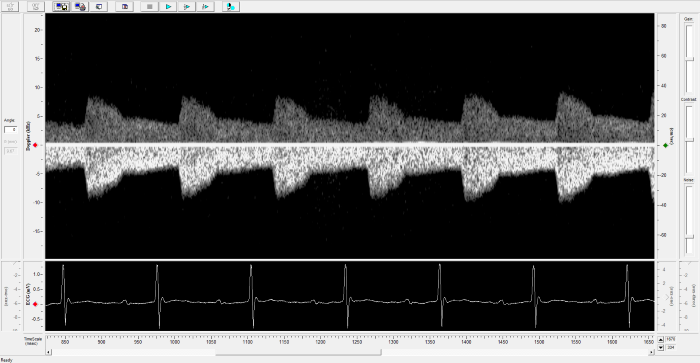

Renal Flow

Renal Flow. Image Credit: Scintica Instrumentation Inc.